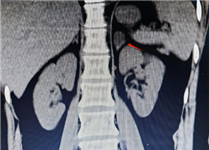

对于肾上腺腺瘤的诊断,需要综合运用多种检查手段。实验室检查如激素水平测定,有助于判断肿瘤是否具有功能性以及分泌的激素类型。影像学检查,如CT、MRI等,能够清晰地显示肿瘤的位置、大小、形态等特征,为诊断和治疗提供重要根据。

如果体检发现肾上腺腺瘤,首先要明确它是否“有功能”:通过CT或MRI明确腺瘤的大小、位置、形态,帮助判断性质。

肾上腺CT正常表现

1.形态:形态各异;右侧:斜线状、倒“V”、倒“Y”形;左侧: 倒“V”、倒“Y”形或三角形;三维重建呈叶状。

2.大小: 侧支厚度<10mm;侧支厚小于同侧膈肌脚,面积小于150mm。

3.密度: 均匀,边缘光滑,无外凸结节。

4.强化: 均匀,边缘光滑。

肾上腺腺瘤CT表现

1.肾上腺腺瘤发生于肾上腺皮质,含脂质;

2.直径多小于3cm;

3.CT值<10HU;

4.出血、坏死、囊变少见;5.CT增强:早期快速廓清